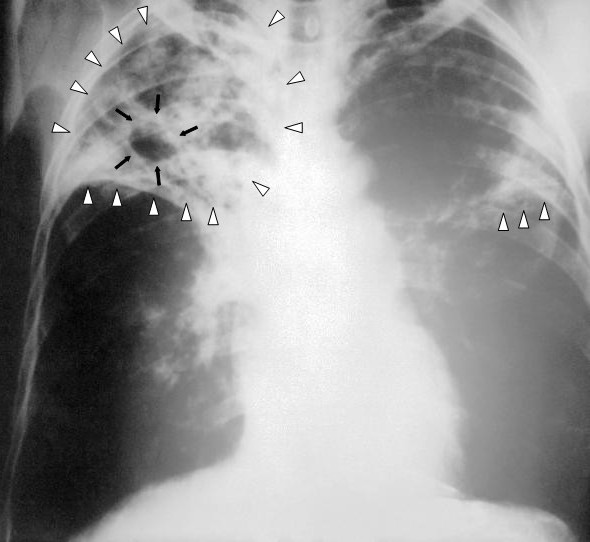

1. Tuberculosis (TB)

Tuberculosis is a bacterial infection most often found in the lungs, but it can also be found in the lymphatic system and other vital organs. TB bacteria cause death of tissue in body organs they infect.

Most people who are exposed to TB never develop symptoms because the bacteria can live in an inactive form in the body — a condition known as latent TB. But if the immune system weakens, TB bacteria can become active, transitioning disease to actual TB. Active TB disease can be fatal if left untreated.